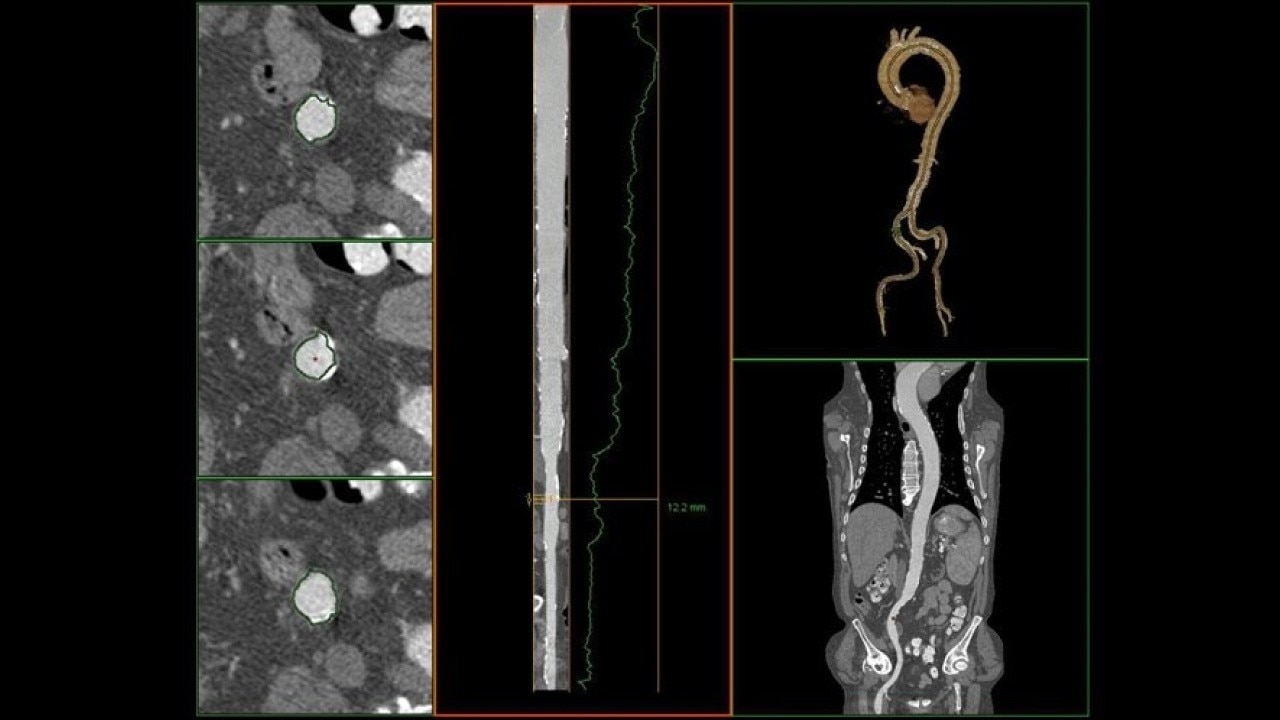

The Valve Planning protocol in the VesselIQ Xpress application lets you visualize cardiac anatomy with the degree of detail required to evaluate the presentation of the aortic valve. Armed with this information, you can develop a pre-procedural TAVR/TAVI plan to establish a therapy strategy for the patient.